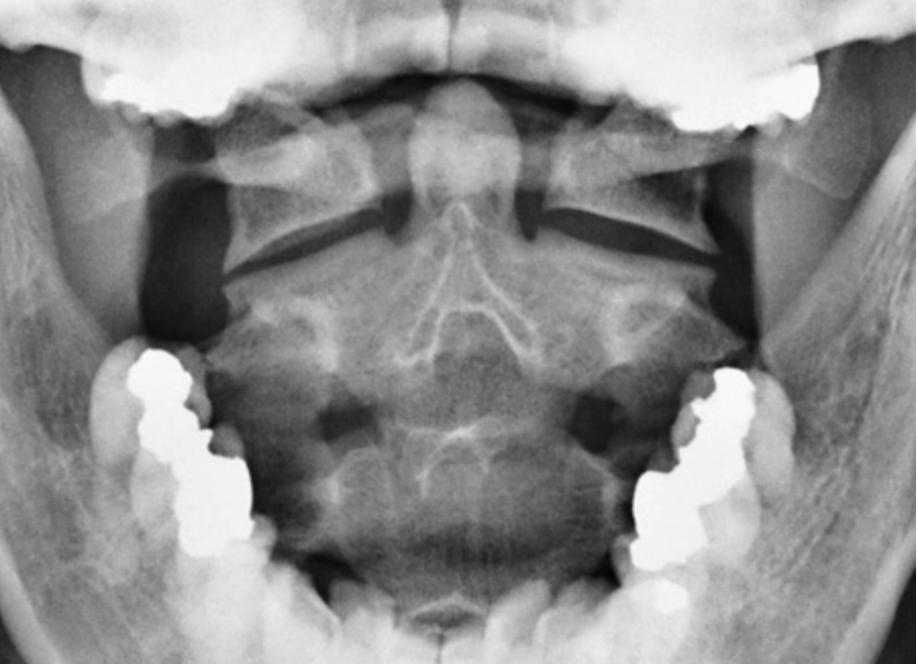

What is this view? What views are missing?

APOM

MISSING

○ AP Lower Cervical

○ Lateral

○ Right and Left Oblique Posterior)

Davis Series ○ Flexion and extension lateral (along with all other films)